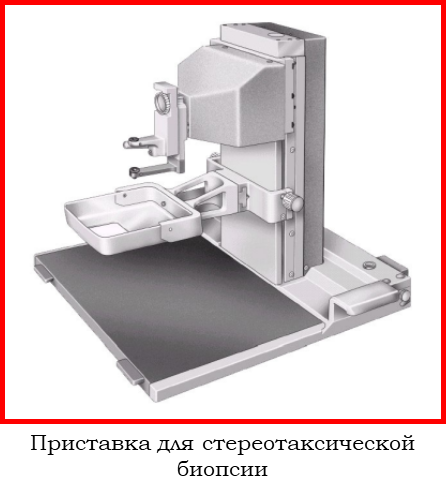

4.3 нет компрессионных пластин для 2D биопсии, нет приставки для стереотаксической биопсии.

4.3 опциональная доступность приставки для стереотаксической биопсии,

Шаг 7. Нужна ли приставка для стереотаксической биопсии?

Приставка для стереотаксической биопсии предназначена для автоматического параметрического расчета и позиционирования держателя биопсийной иглы в точку забора ткани.

В настоящее время сделаны попытки установить точный диагноз злокачественной опухоли до операции, чтобы избежать ошибок при ее позднем выявлении. Для этого используется биопсия молочной железы под контролем рентгена, известная как стереотаксическая пункционная биопсия. Стереотаксическая биопсия образований под рентгеновским контролем по последним данным является безопасным и эффективным методом интервенционной диагностики как злокачественных новообразований, так и доброкачественных процессов.

Перечень необходимого оборудования для проведения стереотаксической биопсии молочной железы следующий:

- Система маммографическая со стереотаксической цифровой биопсийной приставкой.

- Инструментарий для биопсии:

- биопсийный пистолет,

- набор одноразовых игл для биопсии различного калибра и длины,

- по возможности – стул для биопсии или стол для горизонтальной биопсии.

Показания для стереотаксической биопсии молочной железы под рентгеновским контролем:

- непальпируемые узловые образования с признаками злокачественности (BI-RADS 4,5), такими как нечеткие или тяжистые контуры, неоднородная структура за счет кальцинатов злокачественного типа, рост образования в динамике;

- сгруппированные микрокальцинаты без видимого узлового образования (BI-RADS 4,5);

- тяжистая перестройка структуры локального характера с вкраплениями микрокальцинатов или без них (BI-RADS 4,5);

- в зависимости от клинического подозрения и предпочтения пациента поражение, классифицируемое как категория 3 по BI-RADS и визуализируемое только при маммографии, также может быть направлено на биопсию.

Список маммографов с возможностью оснащения приставкой для стереотаксической биопсии: